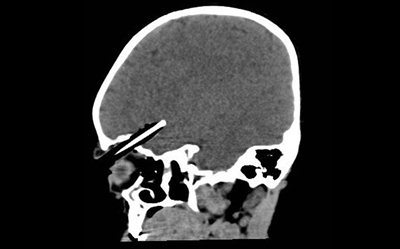

Η μικρή Wren Bowell ήταν άτυχη: καθώς περπατούσε σκόνταψε και έπεσε πάνω στο μολύβι που κρατούσε το οποίο διαπέρασε την κόγχη του ματιού της και «καρφώθηκε» στον εγκέφαλό της.

Ταυτόχρονα η Wren Bowell ήταν πολύ πολύ τυχερή: το μολύβι πέρασε ξυστά από το βολβό του ματιού της και από τρία αιμοφόρα αγγεία και κατέληξε σε βάθος τεσσάρων εκατοστών μέσα στον εγκέφαλό της.

Μεταφέρθηκε εσπευσμένα στο νοσοκομείο του Somerset στη Βρετανία, όπου υποβλήθηκε σε 4ωρη επέμβαση από νευροχειρουργούς για να σωθεί η ζωή της. Μέρος του κρανίου της χρειάστηκε να αφαιρεθεί για να απομακρυνθεί το μολύβι.